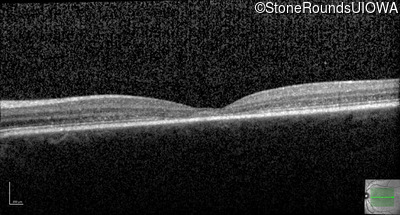

Optical Coherence Tomography - Left - 20/25

Exemplar / OCT Stack